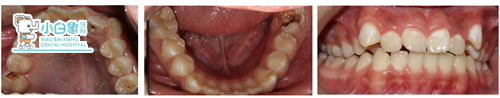

检查:颌面部查未见异常,口内查:牙列不齐,16近中临面龋坏达髓腔,近中缺损至龈下,探诊(-),温度测试无反应,叩(土),牙龈无红肿。36合面大面积缺损,髓腔暴漏,探诊(-),温度测试无反应,叩(+),牙龈无红肿。17,26,27,37,46,47合面龋坏达牙本质深层,探诊敏感,温度测试正常。14,24合面龋坏达牙本质浅层,探诊(-),温度测试正常。15,25,34,35,44,45萌出,窝沟较深,着色,无龋坏。12,22舌侧窝沟龋坏达牙本质深层,探诊敏感,温度测试正常。全口卫生差,软垢覆盖牙面二分之一,牙龈无红肿。

诊断:牙列不齐

g.正畸治疗